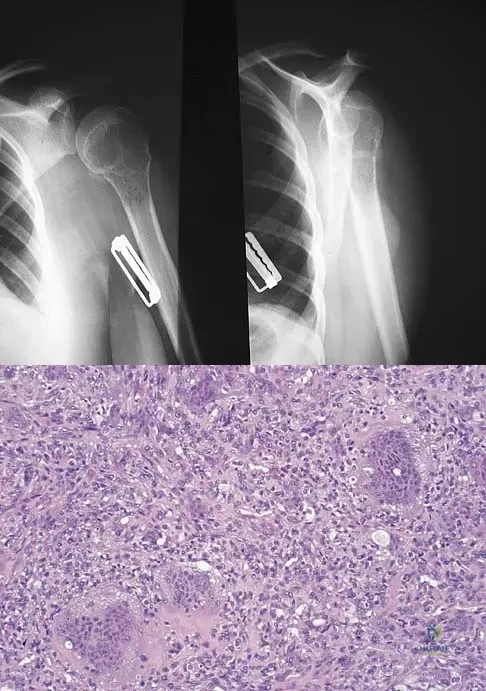

Question 80

A 34-year-old woman reports constant midlateral arm pain after sustaining minimal trauma to the shoulder. Radiographs and a biopsy specimen are shown in Figures 29a and 29b. What is the most likely diagnosis?

Explanation